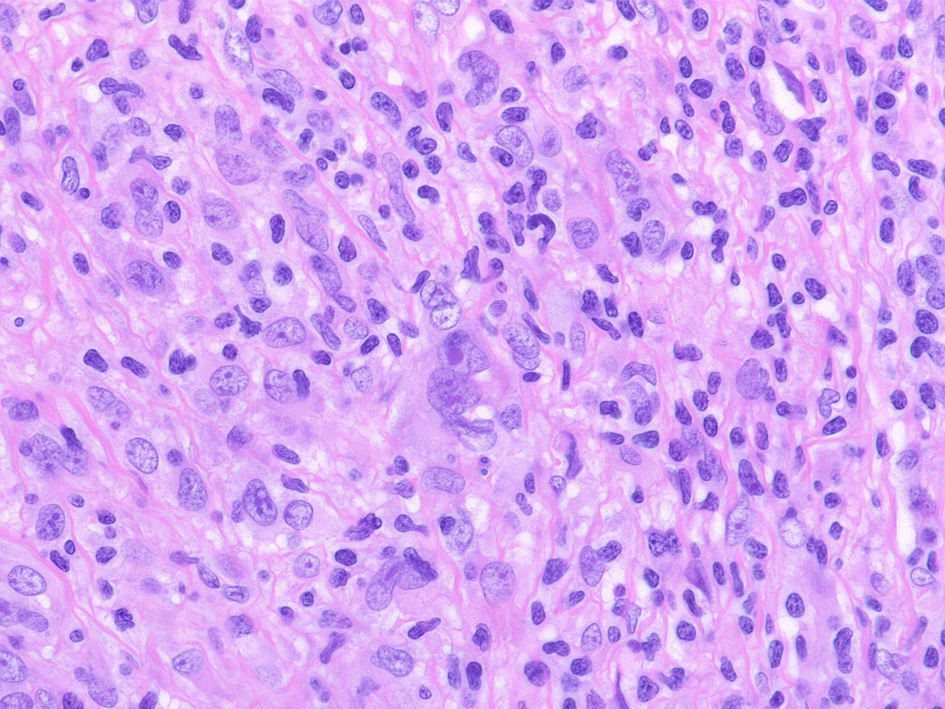

Hodgkin lymphoma-Case02-IWT

74歳男性 左頚部リンパ節腫大

組織球が類上皮細胞様に集蔟して肉芽腫様病変を形成, リンパ節内に明るく見えるエリアができている。HRS細胞が散在。背景はリンパ球, 形質細胞。好酸球が多く見られる

免疫染色

CD30, CD15は陽性, 転写因子のBob.1, OCT2は腫瘍細胞は陰性となる.